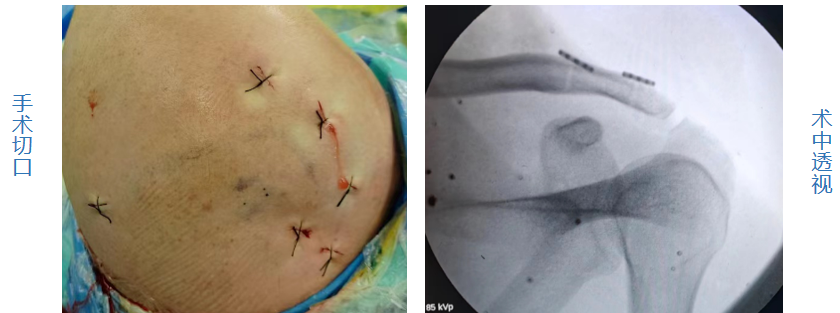

患者外伤后辗转就诊于多家医院,均建议手术治疗,或建议“锁骨钩钢板”固定,或建议“经C臂透视喙突钻骨道袢钢板”固定,但传统锁骨钩钢板后易出现肩峰刺激致肩关节活动受限、肩痛,且需再次手术取出内固定物,而且会发生可能术后再脱位等术后并发症;而对于经C臂透视定位喙突钻骨道袢钢板固定术,在钻取骨道时因为是“盲钻”,血管神经损伤风险较高,且喙突钻骨道后可能出现骨道劈裂甚至继发性骨折等。入院后骨伤科运动馆医学组积极组织讨论,分析各种手术利弊,结合科室关节镜手术优势,决定为患者施行全镜下肩锁关节脱位双带袢钢板(双Endobutton钢板)固定术。该术式在关节镜直视下既可探查关节内情况,直视下钻取锁骨骨道避免血管神经损伤,袢钢板固定时线带是环绕喙突基底部而不经喙突钻骨道,避免喙突骨道劈裂甚至继发性骨折等。术中,肖欢副主任医师及周建军主治医师紧密配合,按既定手术方案为患者施行手术,经过短短的2小时后,手术成功。患者手术后第2天顺利出院。

而双Endobutton钢板是在锁骨和喙突间再一次建立了喙锁韧带相似的解剖构造,更加符合肩锁关节微动的需求,可提供机械稳定,促进韧带愈合。术后避免了固定过程中对肩峰的干扰,从而减少了肩峰下撞击综合征、骨性关节炎、慢性疼痛的发生,可以使患者尽早进行康复锻炼,术后恢复快,减少术后肩关节活动僵硬。关节镜下这一术式具有更清晰的手术视野,直视下钻取骨道减少血管神经损伤风险,且可同时探查处理肩关节内病变,具有微创、出血少、住院时间短、术后肩关节功能良好等优点。